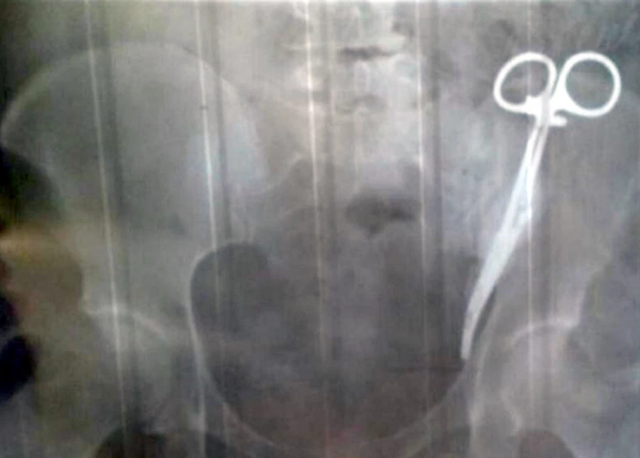

Ezeta Gobeeva, de 62 años y originaria de Rusia, ha estado viviendo desde 1996 con un dolor agudo en su abdomen que los médicos atribuían a un problema de hígado. Nada más lejos de la realidad: la mujer tenía dentro de su cuepo unas tijeras de cirujano.

Sus problemas comenzaron en 1996 cuando los especialistas tuvieron que practicarle una cesárea. Tras años padeciendo dolores insoportables, una radiografía encontró la causa del problema. Durante aquella intervención, una de las tijeras que utilizaron los médicos, quedó olvidada en el interior de Gobeeva por 23 años.

A día de hoy, las tijeras permanecen en su organismo, aunque la mujer ya se está preparando para una nueva operación.